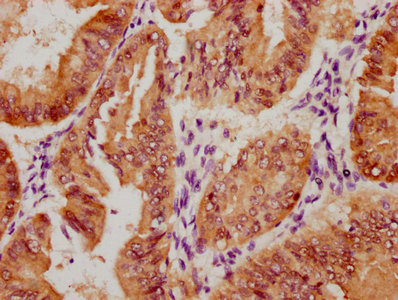

應用范圍:IHC,ELISA

Application Recommended Dilution IHC IHC-p:1:50-300 ELISA 1:10000-20000 -